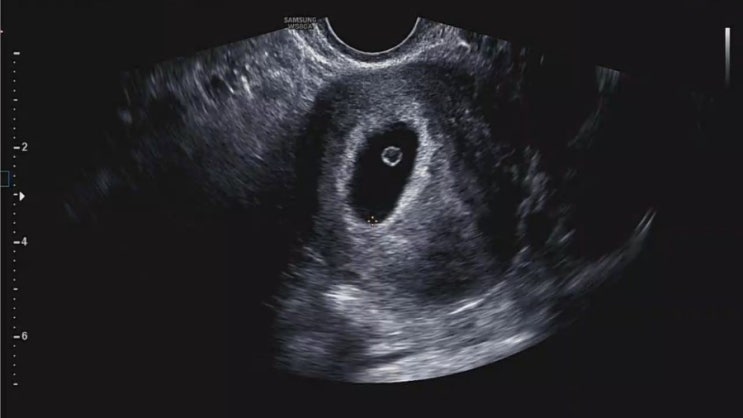

임신기록3 6w2d) 심장소리 듣고 난황까지 확인!

2024.11.12 임신 후 아이소망 산부인과에서 첫 진료를 보고 2주 뒤 두 번째 내원한 날! 이번에는 난황과 심...